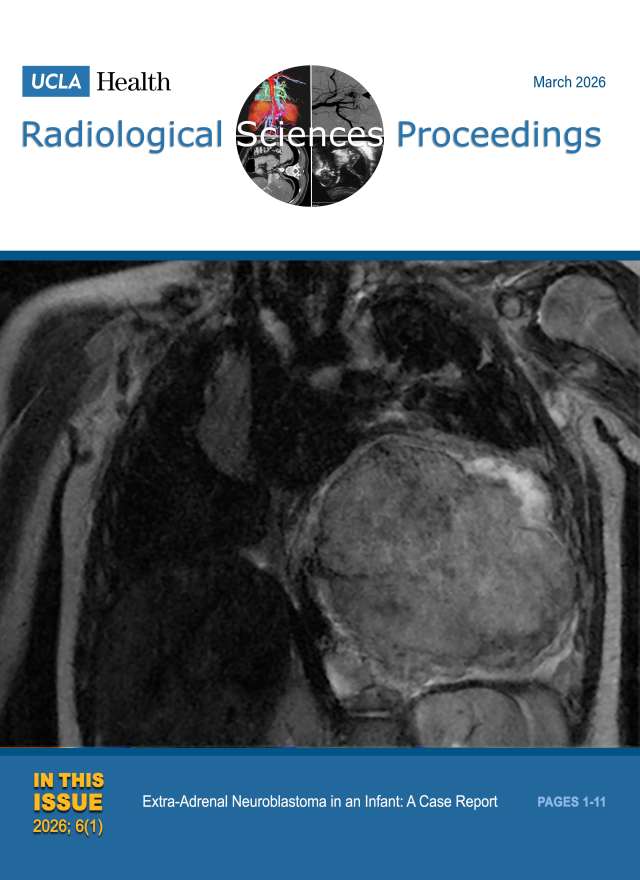

January 2023

Volume 3, Issue 1

- Concurrent Malignant Infantile Osteopetrosis and Hypophosphatasia in a Six-year-old Boy: A Case Report

- A Case Report: Colonic Atresia in a Newborn with Presumed Rubinstein-Taybi Syndrome

- Unilateral Hypertrophy of Tensor Fasciae Latae: A Report of Two Cases

- The Many Faces of COVID-19-Associated Cerebrovascular Disease: A Case Series